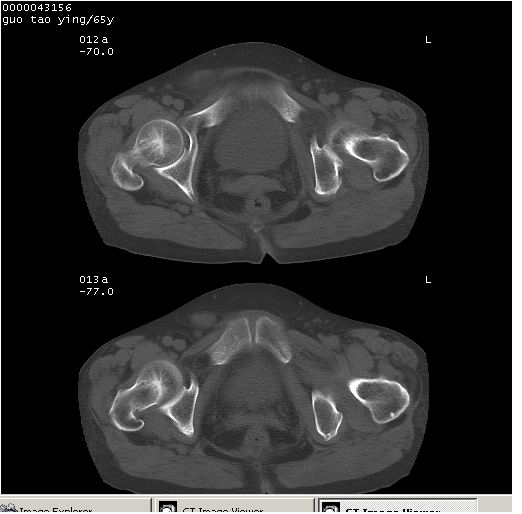

以下是引用黑白光影在2008-1-30 13:22:00的发言:[br]支持左耻骨骨折。[br]未见骶骨骨质明确破坏改变。[br]经楼主提示(勿局限于外伤)。考虑为右侧腹股沟直疝。[br][br][br][br]